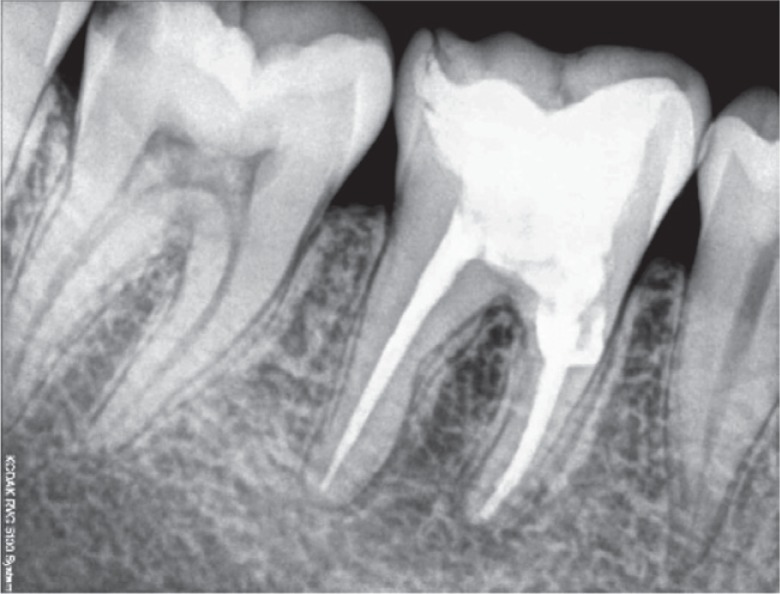

A 25 year old female patient presented to the Department of Conservative Dentistry and Endodontics with a chief complaint of pain in the region of the mandibular right first molar. She reported that an emergency access opening was performed one week prior for the same. Upon clinical examination, extensive destruction of the coronal tooth structure was noted (

Figure 1). Radiographic analysis revealed a periapical radiolucent lesion around the mesial and distal root of tooth #46, and the periradicular dentin at the coronal third of the mesial root was compromised as a result of the poor endodontic access cavity (

Figure 2Preoperative radiograph revealing a periapical radiolucent lesion in the region of the mesial and distal root of tooth #46, as well as compromised periradicular dentin at the coronal third of the mesial root due to a poor endodontic access cavity.